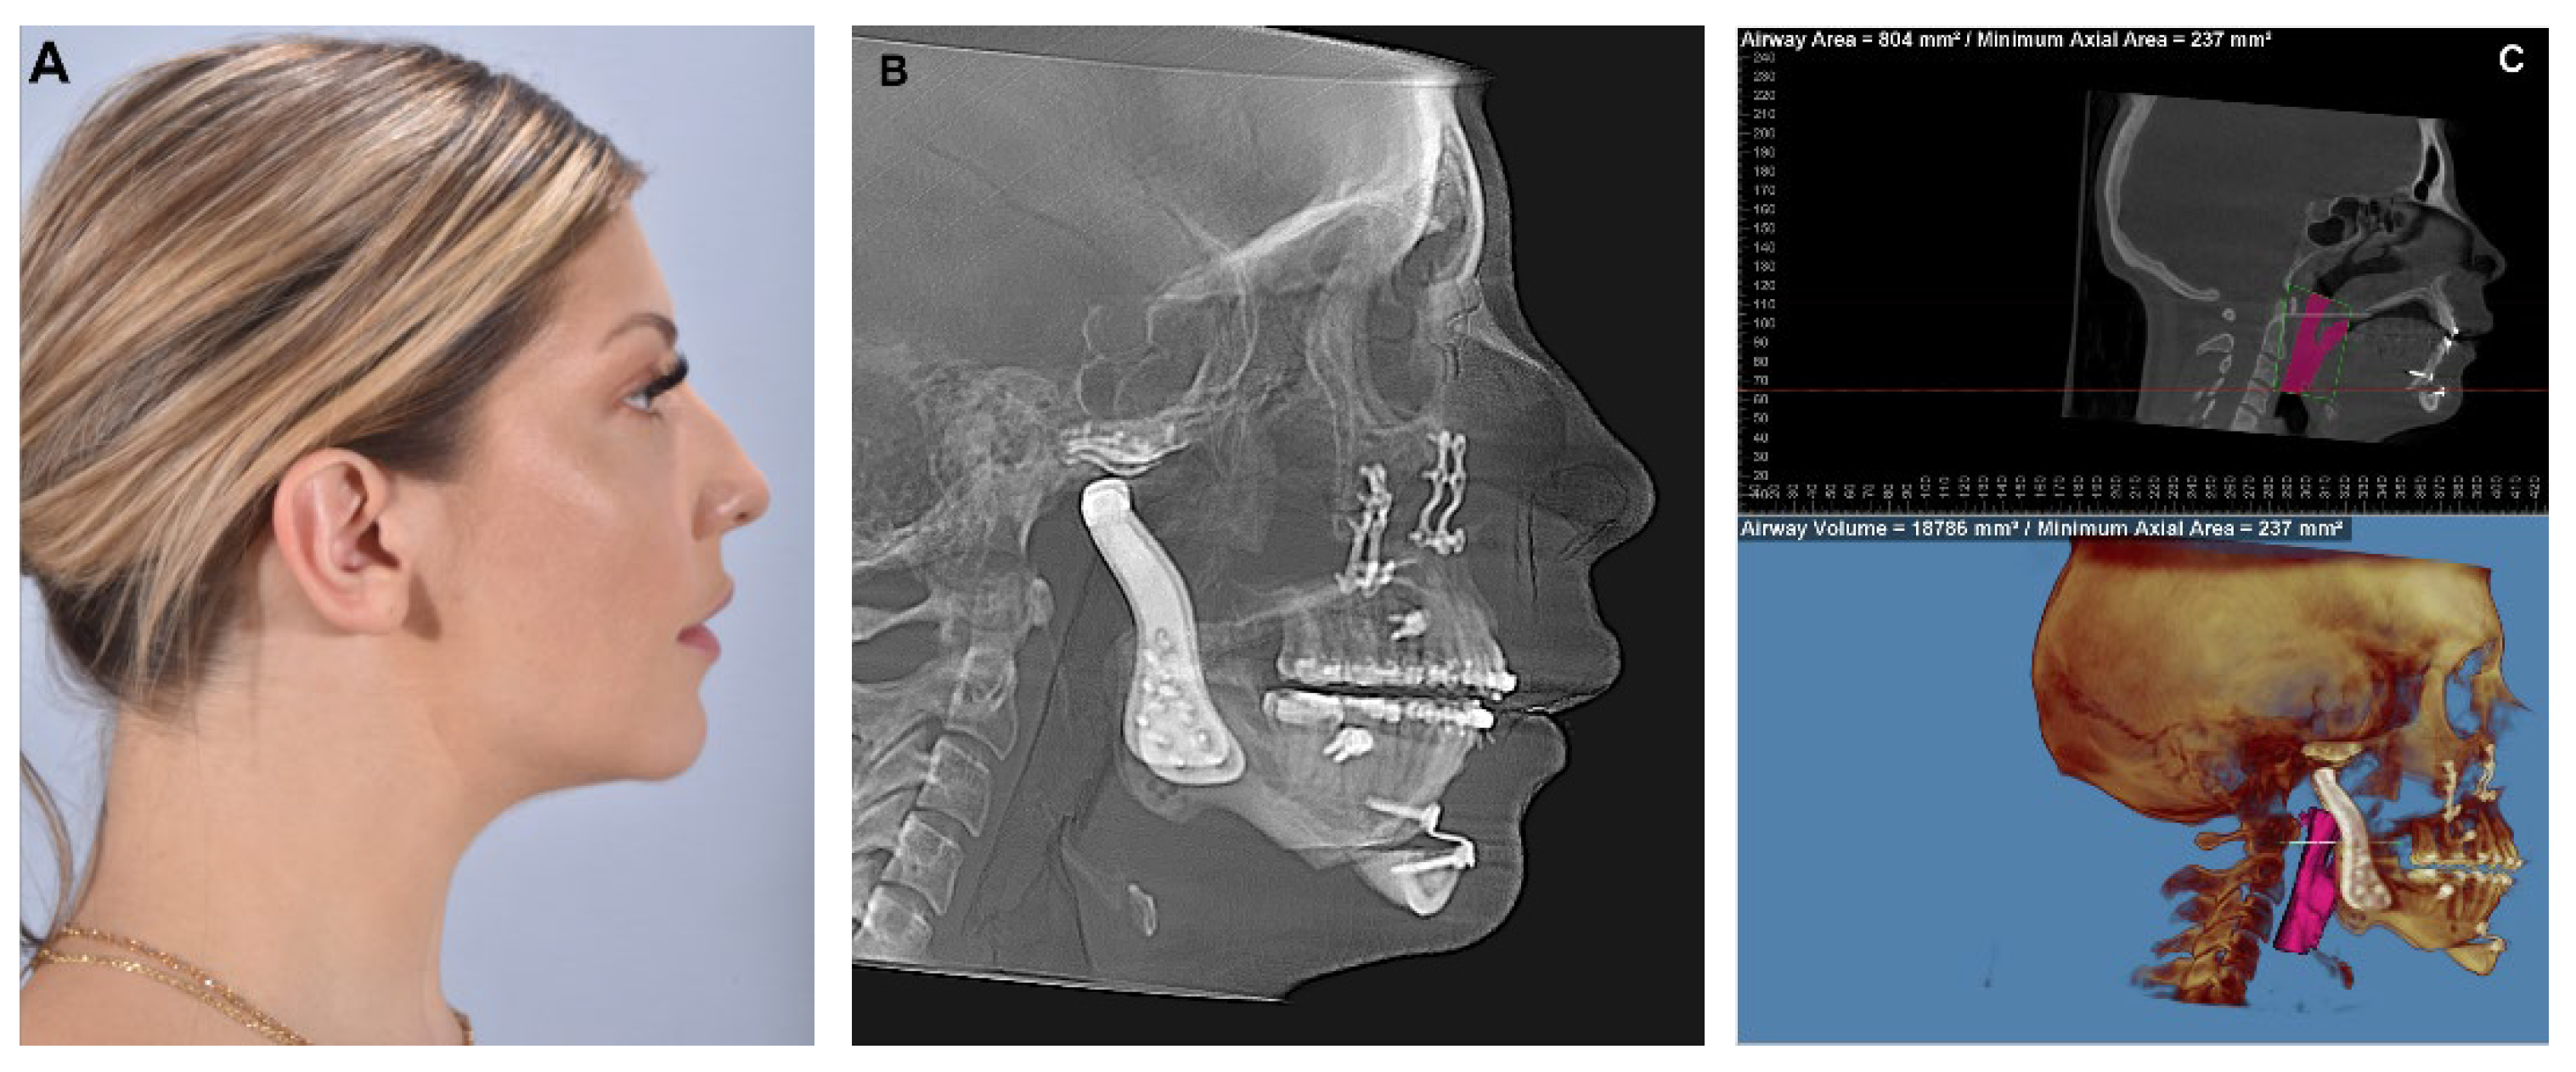

11]. This decision is made following a comprehensive clinical examination, which includes a thorough assessment of the patient’s complaints, expectations and clinical exam including dental models or intraoral dental scans, as well as the utilization of radiographic aids (panoramic Xray, lateral cephalogram and cone-beam computed tomography (CBCT) or computerized tomography (CT) scan) to gather additional information. End-stage TMJ pathology, particularly when condylar degeneration is present, can lead to loss of posterior vertical height and high occlusal plane angles, Class II malocclusions, anterior open bite and decreased airway space (

Figure 1).

For these patients, the combined approach of TMJR with orthognathic surgery not only improves functional aspects (better chewing and opening) but also enhances airway and breathing capabilities, produces superior aesthetic outcomes and can lead to a reduction or even elimination of pain [